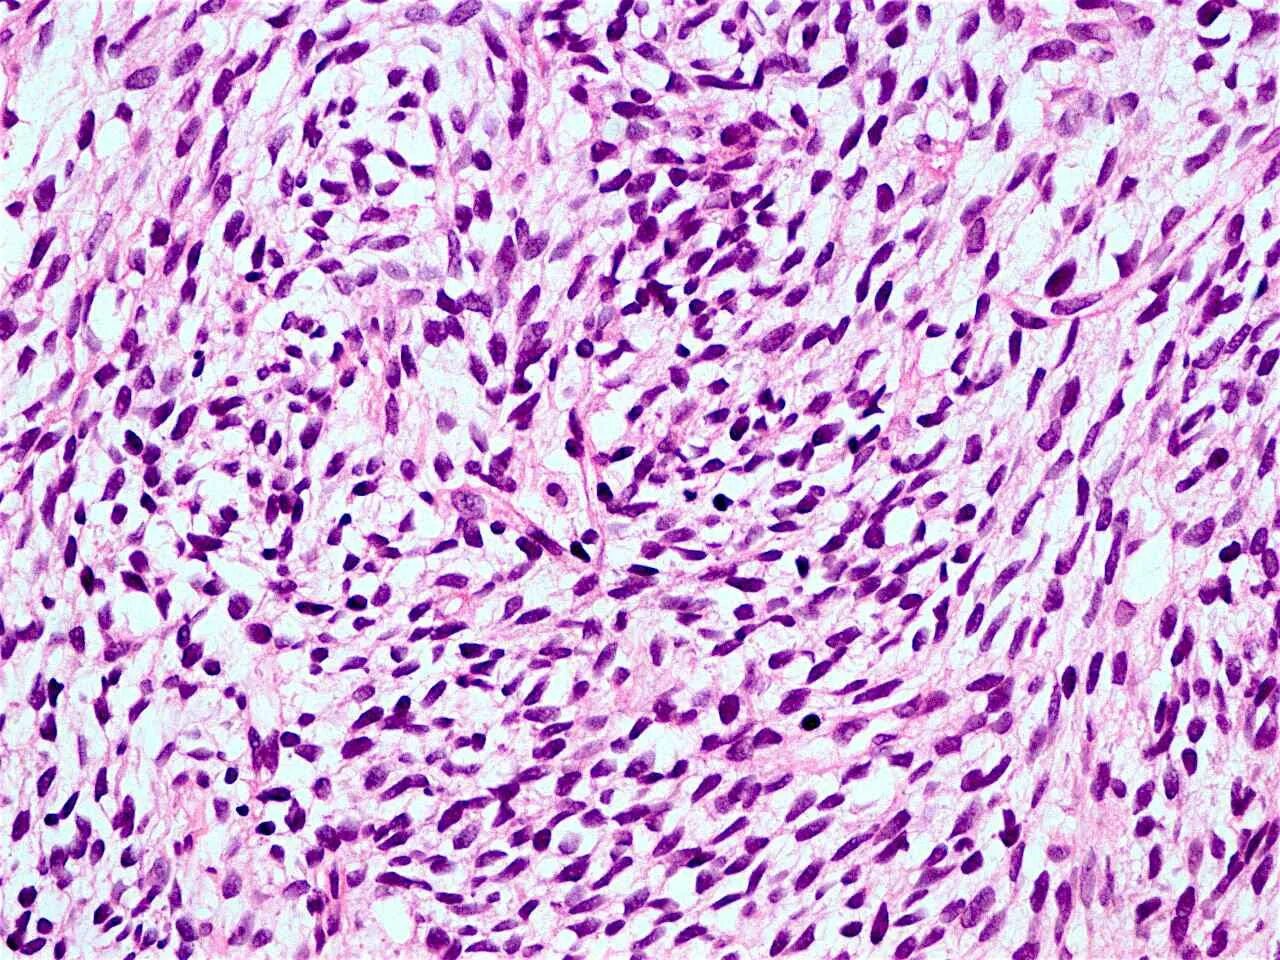

Синовиомы